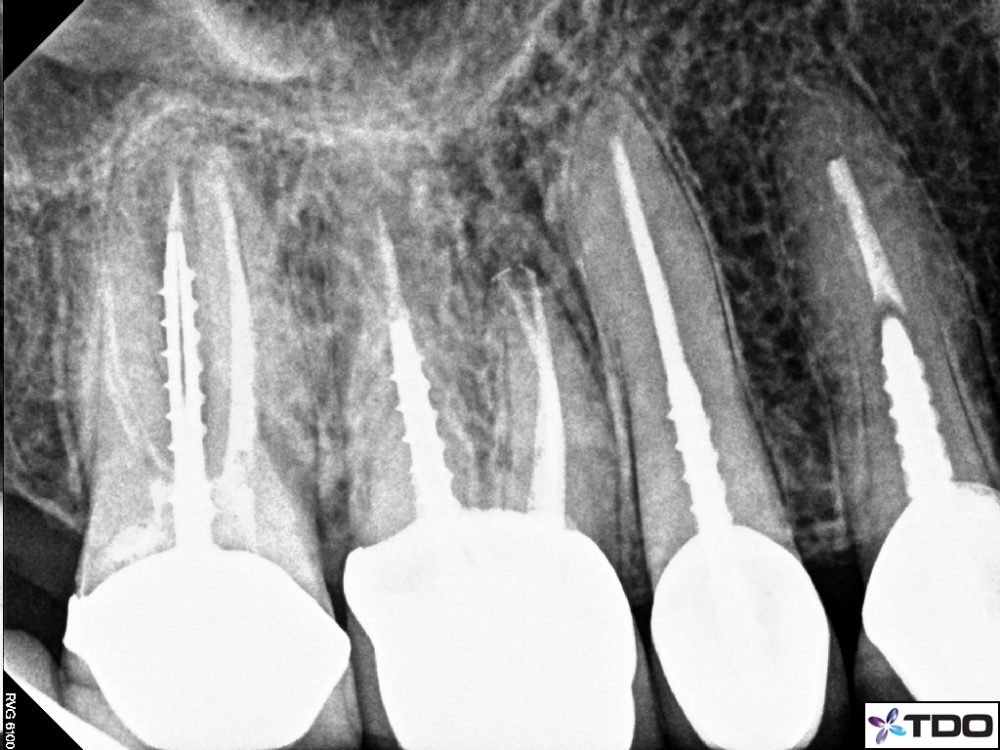

After careful examination it is decide to start the endodontic therapy[Root Canl Treatment[ right away.The root canal is opened and cleaned and a suitable dressing is given.

The aptient reports the next day with absolutely no pain.Other Root Canls are also completed as planned.

Sebsequently Posts are placed and crowns are fabricated.